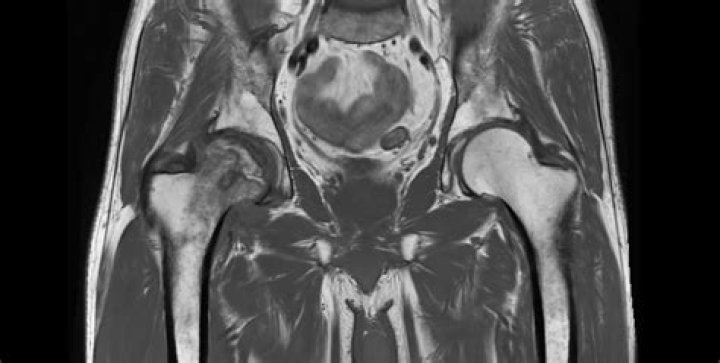

MRI findings of AVN include decreased signal intensity in the subchondral region on both T1- and T2-weighted images, suggesting edema (water signal) in early disease. This relatively nonspecific finding is often localized in the medial aspect of the femoral head. This abnormality is observed in 96% of cases.

MRI is the most sensitive and specific imaging procedure for AVN, of the hip with an overall sensitivity that exceeds 90%. The specificity of MRI is also very high. The use of gadolinium is particularly useful in early detection.

Avascular necrosis (AVN) of hip